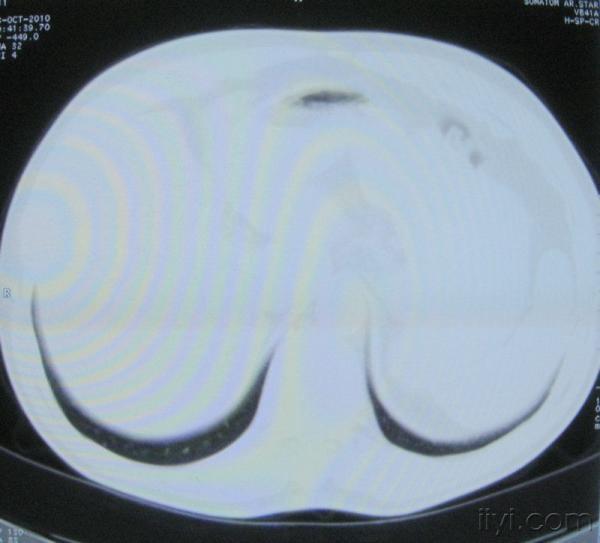

男。60岁,胸片示支气管炎治疗后复查CT。

你指那个肯定是淋巴结,中央系坏死,这很常见,特别在双侧腹股沟会经常看到。这个双侧腋窝及纵隔见多发小淋巴结征。

根据位置考虑应该是淋巴结,密度不均,是因为肿大的淋巴结中心液化坏死